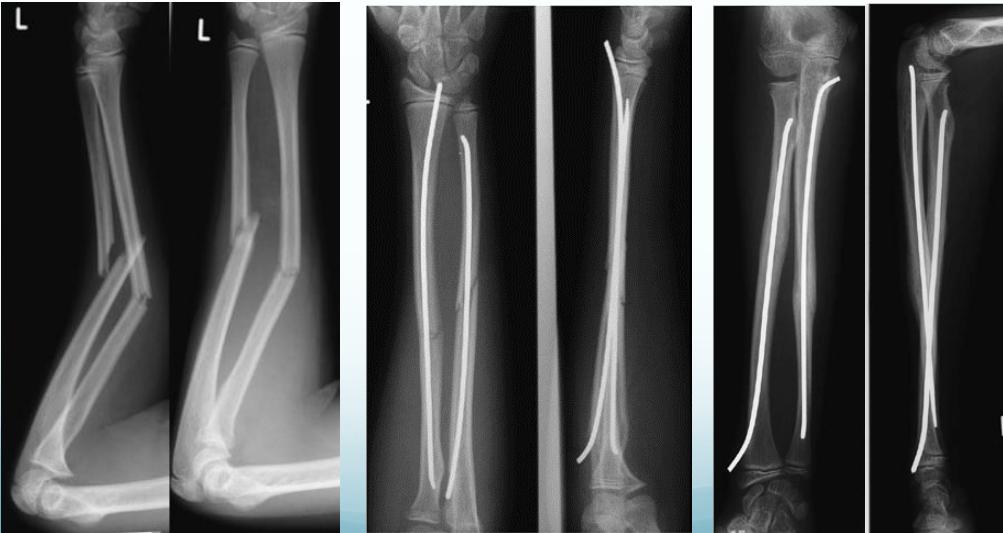

Intramedullary Elastic Nail

- 2 fractures at the same level = 100% unstable

- When unstable or re-displaces in cast

Teddy Slongo, Bern, Switzerland